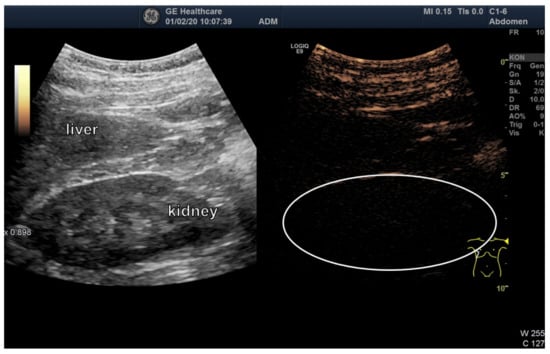

3.3. Ultrasound Examination of Intestinal Absorption